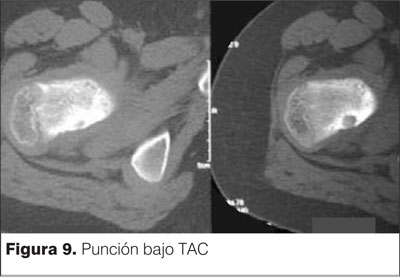

Se decide realizar procedimiento quirúrgico de resección mediante punción bajo tomografía axial computada (TAC). Se muestran las imágenes en las figuras 9, 10 y 11.

La resección en bloque bajo TAC se efectúa en sala de tomografía, en condiciones estériles, con el paciente en ayunas y bajo anestesia general(11). Utilizando cortes finos de tomografía se planifica la aproximación, logrando el trayecto más corto y seguro, libre de estructuras neurovasculares(11). Se puncionan partes blandas y corticales óseas a través del cual se introducen cánulas de calibre creciente(11). Al retirar las cánulas se obtiene material óseo, en el cual es posible reconocer fragmentos del nido(11). Este material se envía a anatomía patológica(11). Con el uso de la resección en bloque bajo TAC, se garantiza la eliminación del tumor pero se debe ser cuidadoso por el debilitamiento que se genera sobre todo en los huesos largos de los miembros inferiores y el riesgo de fracturas patológicas(11).